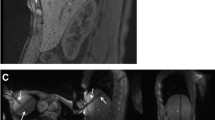

The selected puncture site was labelled with a skin marker before skin disinfection. Local anaesthetics were injected subcutaneously (Xylocaine 0.9 %, AstraZeneca, Wedel, Germany) before a small skin incision was made. Analgesia and sedation were applied intravenously (i.v.) during the intervention (analgesia: piritramide i.v., total dose 8–15 mg or pethidine i.v., total dose 50–150 mg; sedation: midazolam i.v., total dose 3–5 mg); pulse rate and oxygen saturation were monitored. Different commercially available MR-compatible RF systems were used [20]. Twenty-six lesions were treated using an internally water-cooled monopolar RF system with 17-gauge single applicators (Valleylab, Covidien, Boulder, CO, USA). The active tip length varied between 3 and 4 cm. Two grounding pads were placed under the patients’ backs. Nineteen lesions were treated using a 17-gauge internally water-cooled monopolar cluster applicator with three electrodes located on the same handhold (Valleylab, Covidien, USA). The active tip length was 2.5 cm. Four grounding pads were placed beneath the thigh and back of the patients. A total of 168 lesions were treated using internally water-cooled bi- or multipolar applicators (Olympus Celon, Teltow, Germany). In 21 cases, a single applicator was used in bipolar mode. Two applicators were used in 129 cases, three in 16 cases and four applicators were used in 2 cases. Depending on the tumour diameter, active tip lengths of 2, 3 and 4 cm were used. The RF generator and the fluid pump were placed outside the MR suite and connected to the applicators via a cable tunnel. A magnetically shielded liquid crystal monitor placed beside the interventionalist displayed the acquired images within the MR suite. The applicators were placed into the tumour under guidance of MR fluoroscopic sequences. A steady-state free precession sequence which allowed different image weightings to be acquired was used for targeting (BEAT_IRTT sequence, Siemens Corporate Research, Princeton, New Jersey, USA; Fig. 2). A T2-like image weighting was selected if the lesion to be treated was T2 hyperintense or if the visualisation of vessels was considered helpful for orientation or patient safety. T1-weighted images were chosen for targeting T1 hypointense lesions or if previously treated tumour areas required visualising. They were also selected for a number of T1 hyperintense melanoma metastases. Three image planes were selected: two in the plane of the planned applicator track and a third positioned orthogonally to the others. The three images were displayed parallel on the same screen; the update rate of a single slice was 330 ms. Sequence details are given in Table 1. Targeting was performed in one or two steps with intermittent pauses for image monitoring, if necessary. In no case did the procedure have to be aborted as a result of inability to target the lesion. The T1-weighted images acquired during these pauses were used to readjust the slice orientation or needle position. Singular RF applicators were positioned centrally into the target lesion; if two or more applicators were used, these were positioned circumferentially. Energy application was adapted according to the guidelines of the manufacturer, pain level and the size of the active tip. During energy application, the increase of impedance, indicated by a decrease in current level or power output, was considered a sign of advanced coagulation near the applicator position. After 10–20 min of energy application, preferentially T1-weighted images were acquired to visualise the developing ablation zone and to check for remaining tumour tissue. Energy application was continued if remaining vital tumour tissue was suspected or if the expansion of the T1 hyperintense ablation zone did not include a safety margin of at least 5 mm of healthy liver tissue (Fig. 3). The applicators were repositioned to enclose the entire tumour within the ablation zone if a further expansion of the zone could not be achieved otherwise. Applicator retraction was performed under coagulation. The duration of energy application and, if available, the applied energy were registered.

a Coronal slice of a predominantly T1-weighted steady-state free precession sequence of the same patient. A second applicator (arrow) is directed to the same tumour and will be placed caudal to the first applicator. A part of the tumour can be seen caudal to the tip of the first applicator (arrowhead). b A predominantly T2-weighted steady-state free precession sequence with parallel display of a transversal, a sagittal oblique and a coronal oblique image slice used for targeting a second applicator (arrow) close to a branch of the portal vein which has to be crossed to reach the target region (arrowhead)